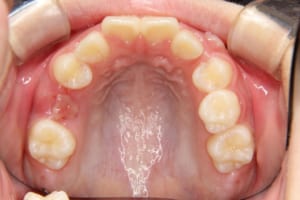

治療前

| 年齢・性別 | 11才 女性 |

| 主訴 | 八重歯の生え方が気になる |

| 使用した装置 | 子どもの矯正治療(前期治療) 緩徐拡大装置 マルチブラケット装置 大人の矯正治療(後期治療/成人矯正治療) マルチブラケット装置 デーモンブラケット シルバーワイヤー 歯科矯正用アンカースクリュー(2本) ホールディングアーチ トランスパラタルアーチ |

| その他/備考 | 上の犬歯が生えるためのスペースが全くない状態でした。放置すると重度の八重歯になることが想定されるケースです。 今回はあごの成長も利用しながら治療をするために、早めに後期治療(大人の矯正治療)に移行しました。 治療後レントゲン写真を見たところ、上顎前歯に若干の歯根吸収を認めました。 |